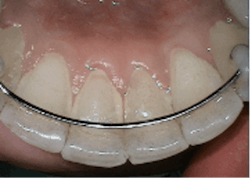

- Sodium bicarbonate powder for the removal of heavier stain supragingivally Glycine powder for supra/subgingival access with a standard nozzle that reaches PD up to 4 mm and subgingival nozzle for PD up to 5 mm.1 A flexible narrow tip is attached to the subgingival nozzle to allow for subgingival access with minimal tissue distention (figure 2).1,3,6

Conservation of tooth structure

Air polishing conserves tooth structures with studies showing similar root effects as ultrasonics, which cause 50% less alterations, roughening, scratching, and gauging of root surfaces than hand-activated instruments.1 All glycine and erythritol air polishing powders have a very low Mohs hardness rating (2-3) and are more uniformly shaped than polish paste of any grit size, leading to less abrasivity.1,8,9